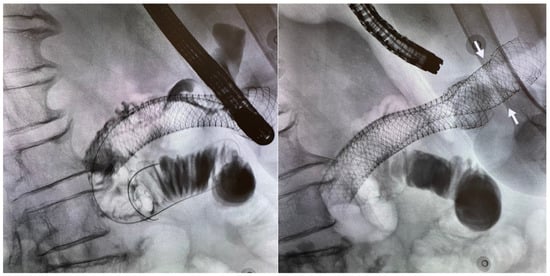

5.2. Stent Selection

5.4. Endoscopic Gastroenterostomy

6.2. Gastroduodenal